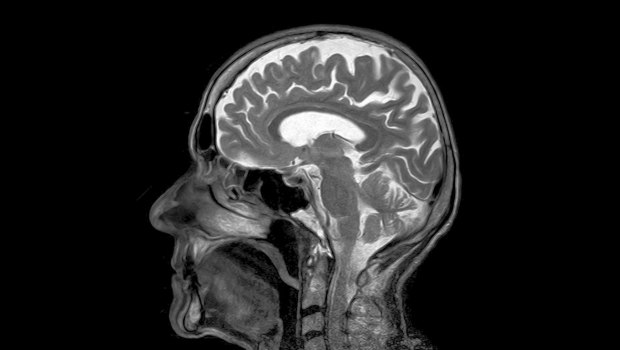

Το τεστ μετρά τα επίπεδα μιας «φωσφορυλιωμένης» μορφής της πρωτεΐνης ταυ, η οποία σχηματίζει παθολογικά συσσωματώματα στον εγκέφαλο των ασθενών με Αλτσχάιμερ.

Στις περιπτώσεις αυτές, απαντήσεις μπορούν να δοθούν μόνο με εξειδικευμένες και ακριβείς εξετάσεις όπως αναλύσεις του εγκεφαλονωτιαίου υγρού και τομογραφία εκπομπής ποζιτρονίων.